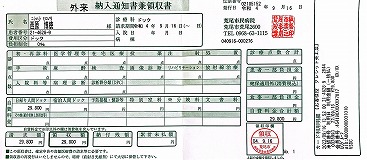

092 病院定期検査

2024-0210西原クリニック検査結果

090 脳ドック

2024.18.14 荒尾市民病院 2023.08.10 荒尾市民病院

2024 PDF 2023 PDF

22.9.16 荒尾市民病院

2014(H26)7.29 岡山淳風会